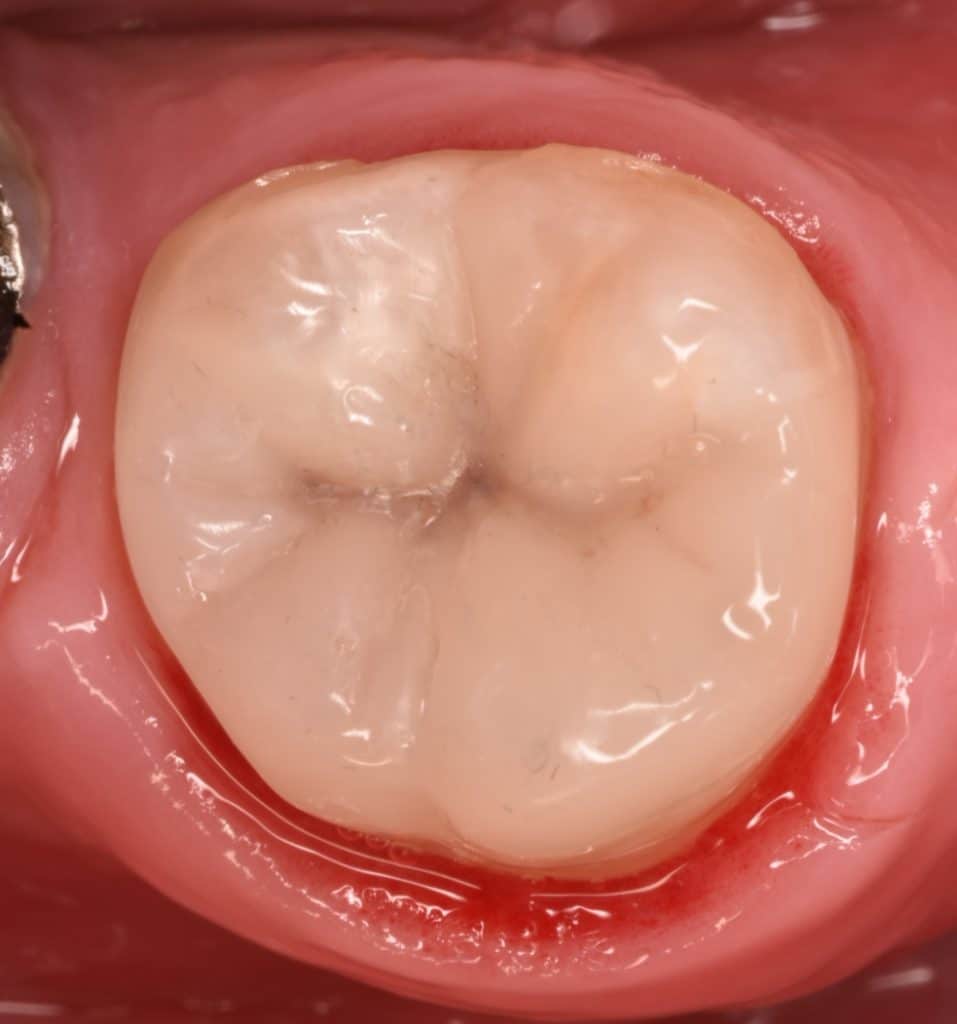

Initail state showing the old defective amalgam ,distobuccal wall fracture

Isolation with rubberdam by using active wing clamp for subgingival placement of clamp

Immediate result

Slight finishing and polishing

Immediate after rubberdam removal